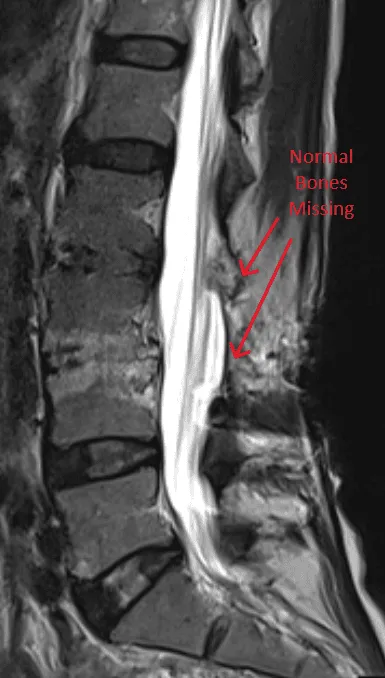

MRI of the spine showing missing vertebrae, marked by red arrows.

Highly Invasive

MRI image of a spine showing untreated herniations marked with arrows.

Herniated Discs Not Treated